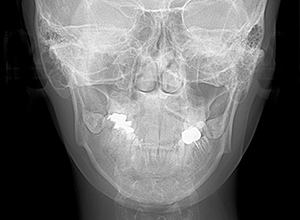

FP・IOP

X-Ray

X-Ray所見

セファロ所見 下顎骨体部は小さくないものの下顎枝は短く、下顎頭は後方に位置付き中顔面高は高いため、下顎はクロックワイズローテーションしており、前後的にはII級の骨格形態を示していた。

パノラマ所見 上下顎両側第三大臼歯は埋伏していた。下顎右側大臼歯から犬歯まで近心傾斜し、左側においては左下5を境に大臼歯は近心傾斜、近心の歯は遠心方向へ傾斜が認められた。